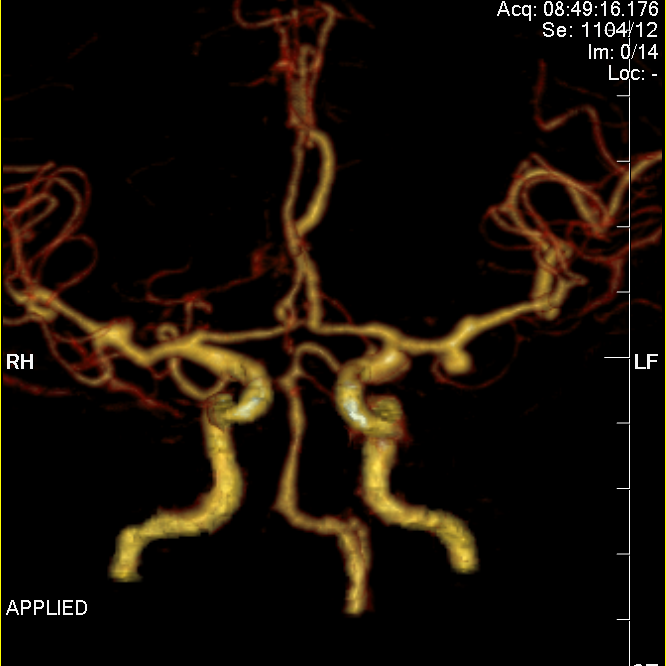

脑动脉CTA示左侧大脑中动脉M1段动脉瘤、左侧大脑后动脉P3段动脉瘤。

左侧颈动脉极度迂曲。

通桥银蛇®DA远端通路导引导管轻松至海绵窦段。

支架导管、微导管到位,通桥银蛇®DA远端通路导引导管稳定支撑。

支架半释放;继续填圈;通桥银蛇®DA远端通路导引导管稳定支撑,术毕。

动脉瘤填塞满意;支架展开良好。